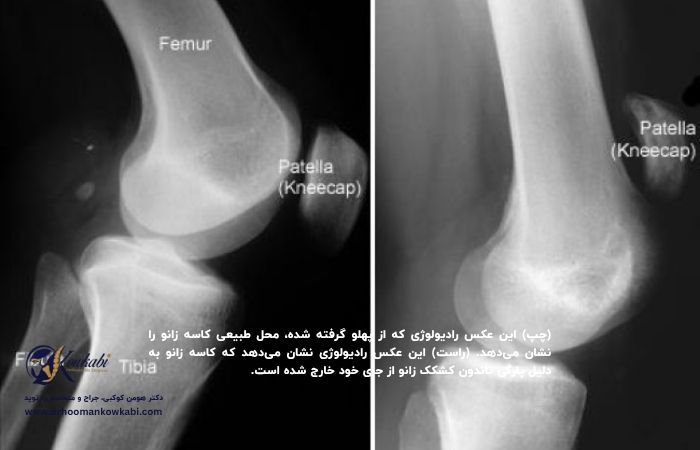

برای تأیید تشخیص، پزشک ممکن است آزمایشهای تصویربرداری مانند اشعه ایکس یا اسکن MRI تجویز کند:

اشعه ایکس: در صورت پارگی تاندون زانو، کاسه زانو از جای خود جابهجا میشود که اغلب در تصویر اشعه ایکس از نمای جانبی زانو بهوضوح قابلمشاهده است. پارگیهای کامل معمولاً با اشعه ایکس بهتنهایی قابلتشخیص هستند.